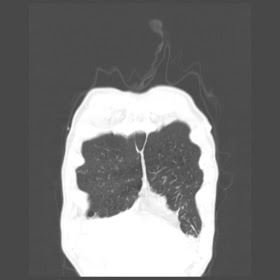

A 52 Years old man suffering with chest pain since 3 years

HRCT Chest